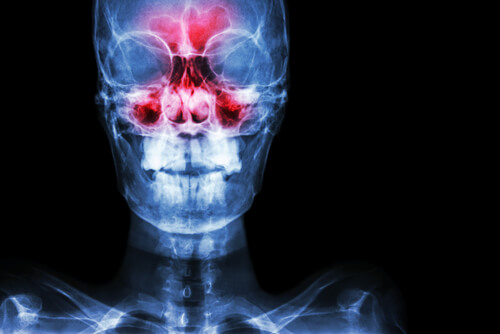

Sinusitis Symptoms: From Origin to Diagnosis

Sinusitis is inflammation of the paranasal sinuses. These are two small, hollow spaces through which air passes to circulate between the bones of your nose. There are several sinusitis symptoms to note.

The sinuses are divided into three groups: frontal, ethmoidal, and sphenoid and maxillary sinuses.

However, when the sinuses become inflamed, breathing gets more difficult and other sinusitis symptoms can arise, such as pain that can be very intense.

If your sinuses are healthy, there is no presence of bacteria or other organisms. In this case, mucus can flow in or out of your nose without a problem. When too much mucus builds up or there is a blockage of the paranasal openings, a breeding ground is created for various types of microorganisms. This can wind up causing sinusitis.